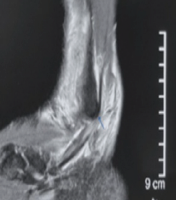

Medial third clavicle fractures associated with posterior dislocation of the distal clavicle present a diagnostic and therapeutic challenge. Initial clinical evaluation with standard radiographs can be misleading, making advanced imaging (3D CT) essential for confirming the diagnosis [5]. Conservative treatment may be appropriate for stable fractures; however, in our case, the progression of deformity and confirmation of posterior dislocation necessitated surgical intervention to ensure optimal functional recovery and prevent long-term complications [6]. This case highlights the importance of thorough clinical and radiological evaluation, with advanced imaging in cases of suspected complex dislocations. Close radiological follow-up is crucial to monitor fracture evolution and clavicular stability. Timely surgical intervention is recommended in cases of progressive deformity and joint instability, which can be performed through open surgery or arthroscopically using simple wires and/or endobuttons [7,8,9]. The patient underwent surgery with a favorable post-operative outcome and a rehabilitation protocol aimed at complete functional recovery [10] (Fig. 5). After a 6-month follow-up, the patient had excellent results for shoulder range of motion and function. The patient’s Constant-Murley score is 92.

Figure 5: Post-operative radiographic control.